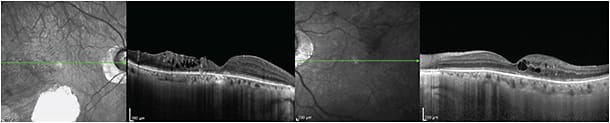

Retinitis pigmentosa produces atrophy of both the retina and underlying choroid, with decreased choroidal blood flow and velocity. A study of 67 eyes with an average of 27 years of RP showed thinner choroids than controls (215.6 µm vs 336.60 µm) (Figure 4, page 58).41

Figure 4. Retinitis pigmentosa. A 48-year-old man with a history of RP for more than 30 years had VA of finger counting OD and 20/20 OS, with severely constricted visual fields in both eyes. The patient has two sisters with RP as well. Diffuse retinal and choroidal atrophy in both eyes appear on EDI-OCT.

Eyes with early diabetic retinopathy may have slightly thinner or normal choroidal thickness, which increases in thickness with disease progression (Figure 5, page 58) and then thins after laser photocoagulation. In macular edema, the choroid may be thicker, thinner, or the same.42,43

Figure 5. Proliferative diabetic retinopathy with cystoid macular edema in a 53-year-old man with a history of diabetes for more than 20 years and BCVA of 20/40 OD and 20/30 OS. The patient underwent three intravitreal injections of bevacizumab and focal laser in the left eye. The underlying choroid is thickened under the areas of retinal edema.